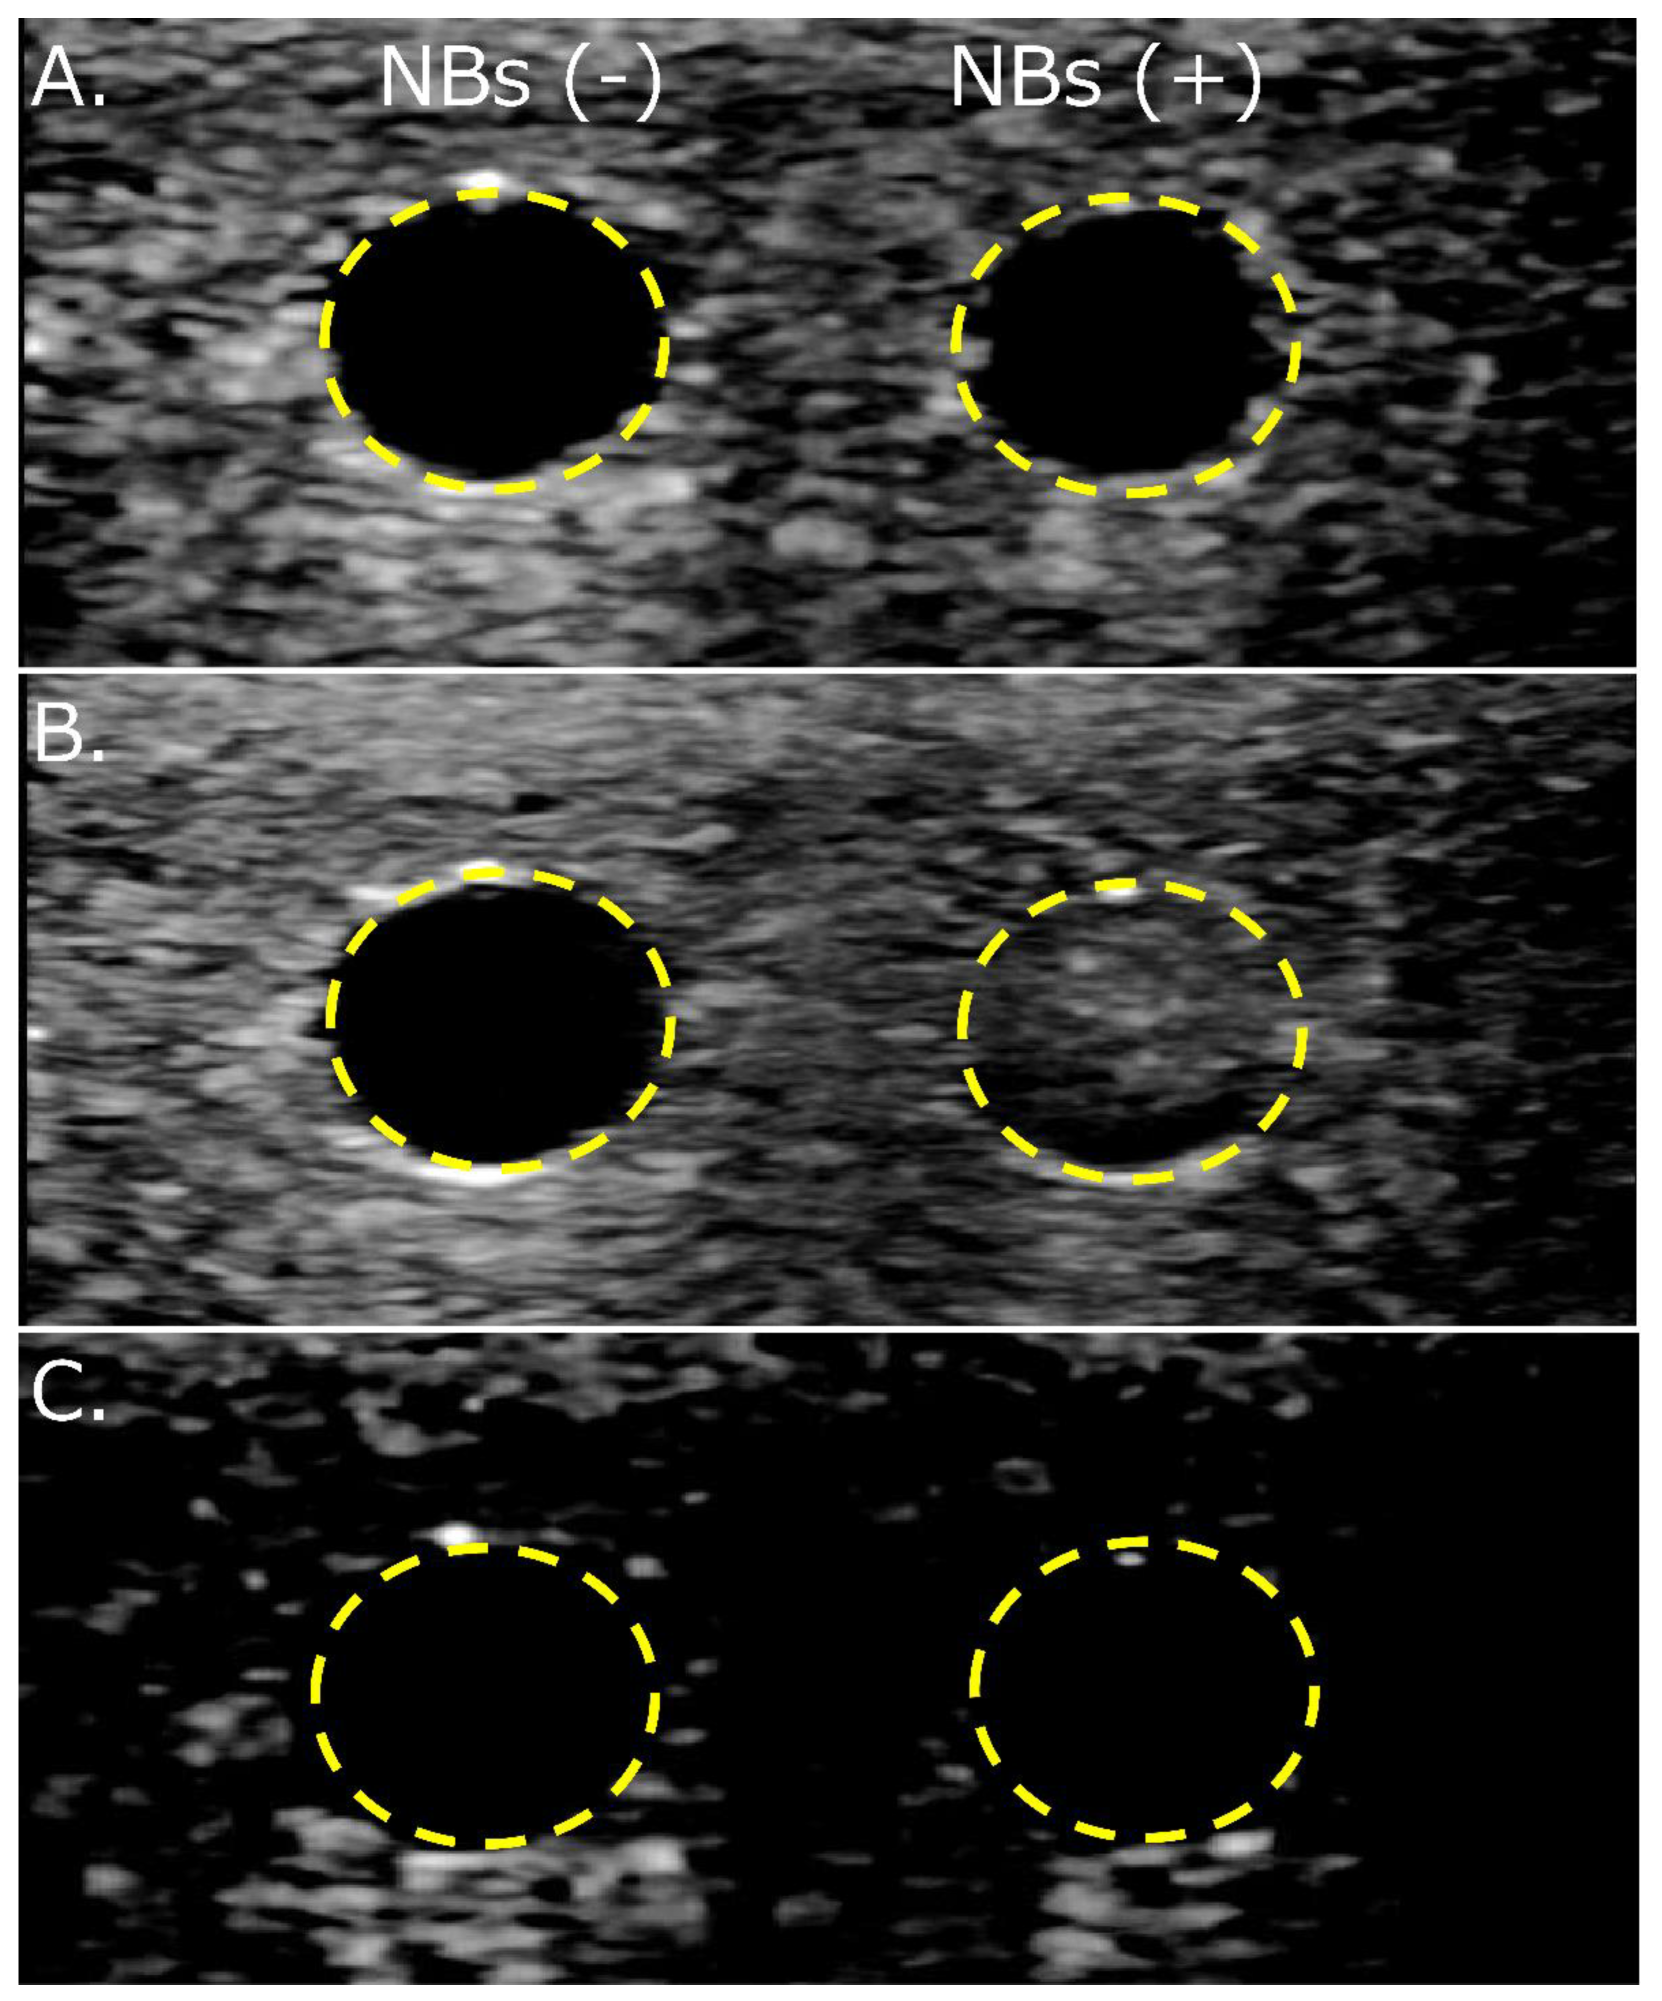

3.4. NBs Regenerated after Lyophilization Are Echogenic

3.5. NBs Regenerated from Lyophilized Materials Act as Cavitation Nuclei in mRNA Sonoporation